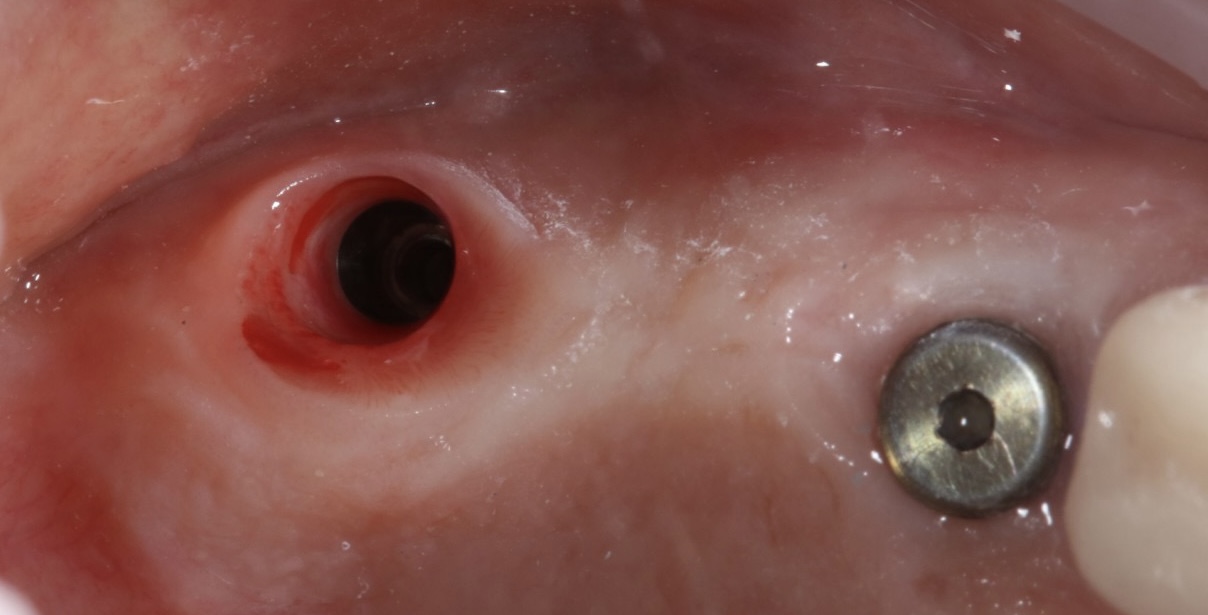

Implantati mogu da budu terapijsko rešenje u različitim situacijama - od nadoknađivanja pojedinačnih zuba u estetski najzahtevnijoj regiji kao što su prednji deo gornje vilice, preko nedostatka vićeg broja zuba pa do full mouth rekonstrukcija, gde se nadoknađuju puni zubni nizovi bilo u jednoj ili u obe vilice ALL-ON-4 ili ALL-ON-6 konceptom.

Naš tim je dovoljno iskusan i stručan za iznalaženje svih ovih rešenja pri čemu se vodimo modernim planiranjem gde željeni oblik i položaj buduće nadoknade diktira položaj implanta, što je imperativ u modernoj implantologiji.

Nekada je ugradnja implanata jednostavna, a nekada je kompleksna i zahteva dodatne hiruške procedure različitog nivoa složenosti da bi se dobili optimalni uslovi za hirurgiju. Naš tim ima znanja, veštine i tehničke mogućnosti za izvođenje svih tih procedura gde se koriste zamenici za kost (“veštačka kost”), kost samog pacijenta, razne vrste membrana (veštačkih ili dobijenih iz krvi samog pacijenta), kao i primena faktora rasta izdvojenih iz krvi sve u cilju dobijanja najboljih uslova za ugradnju implanata i za kasnije protetsko zbrinjavanje kada se pacijent estetski i funkcionalno rehabilituje.